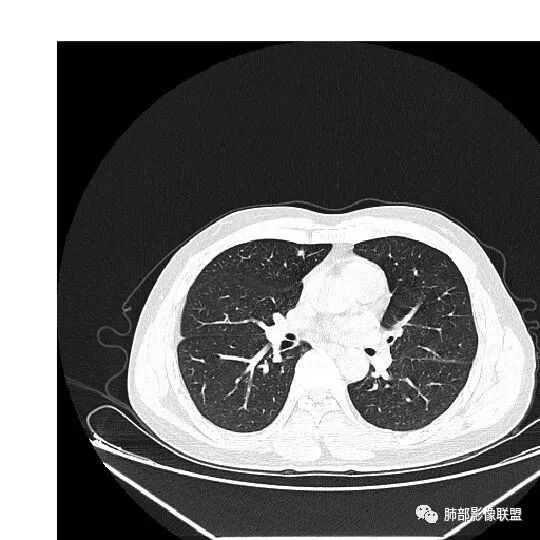

群内讨论

杨泽锋:很难通过一次CT检查来判断小结节的性质炎性结节可能大理由:病灶很小但是很密实毛刺比较长百事可乐:右肺中叶内侧段实性小结节,毛刺、分叶,胸膜牵拉。考虑MIA。李:实性结节,形态不规则,考虑炎性肉芽肿紫气东来:右肺中叶实性结节,毛刺分叶,考虑恶性。穿越七海的风:右肺上叶近胸膜下小结节,实性度较高,肺内淋巴结吧,可随访观察张帅:晨读,右肺上叶前段小结节病变,病灶内可见细支气管穿过,局部血管略增粗,病灶边界清,可见软毛刺,3月胸CT较2月貌似密度减低,毛刺变小,考虑良性病变,炎性病变?春秋:患者51男性,右上叶前段结节,形态不规整,明显分叶,前后变化不明显,考虑恶性!Yiren  Sishui(厶水伊人):小结节,密度较实,有多条线状影,胸膜下分布,肺内淋巴结?炎性肉芽肿?建议随访。东哥:晨读:右肺上叶小结节,不规则,可见分叶,整体收缩,两次CT变化不明显,先考虑良性可能我心飞翔:右上肺实性结节,长毛刺,考虑良性病变王秀仙:晨读:右肺上叶结节,边缘毛刺,一个月后,病灶略有增大,边缘小叶间隔阻挡,考虑腺癌。Shelia🌞:晨读,右肺上叶前段胸膜下小结节,形态不规则,以平直收缩为主,可见u型凹陷,长毛刺,1月复查感觉变化不大,考虑炎性病变,建议继续随访复查除外腺癌一切∮随缘:晨读病例:     右肺上叶前段可见一不规则结节,边缘可见分叶,毛刺,清晰的GGO,近端牵拉血管树,未见明显支气管截断,中年男性,体检发现,综合考虑微浸润腺癌,待排炎性肉芽肿,建议短期随访。

Ao..葉偲雨!👑:右肺中叶内侧段小结节,边缘毛刺,部分层面平直,第二次复查有凹陷,密度似乎比之前淡泊一点(肿瘤的生长周期一个月一般不会有太多变化),大小范围基本稳定,LU-Rads 4a类,炎性结节可能,建议3个月后复查或pet

南边分析

南边:51岁男性,体检发现右肺结节这个年龄段的男性,啥都可以发生,也属于肺癌的高危人群南边:首先是实性还是GGO?好像实性吧

如果实性病变,边缘收缩,可以考虑炎性, 但是边缘有边界清楚GGO,一定要警惕恶性,还有粗短毛刺更要小心撇开其它,看到这个图,除非你怀疑假象,不然就是要考虑腺癌的可能

边界清楚GGO,短毛刺,这要小心瘢痕癌可以多为腺癌复查没变化,与血供有关,属于休眠期张国祯教授的理论:腺瘤样增生、原位癌都属于偏良性,就是没有侵袭性;以后发展——侵袭可以,不变可以,部分可能还会凋亡(比较少)

结果

原位腺癌